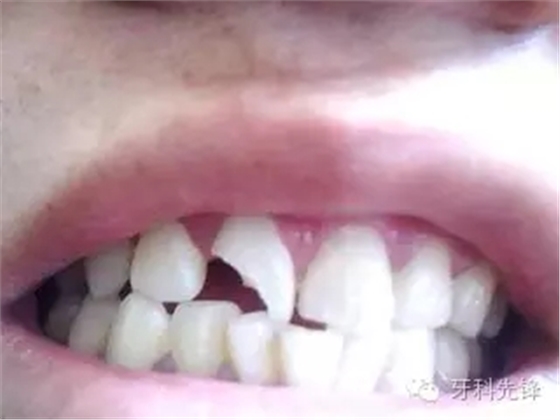

口腔里面的照片,牙齒位置較高,